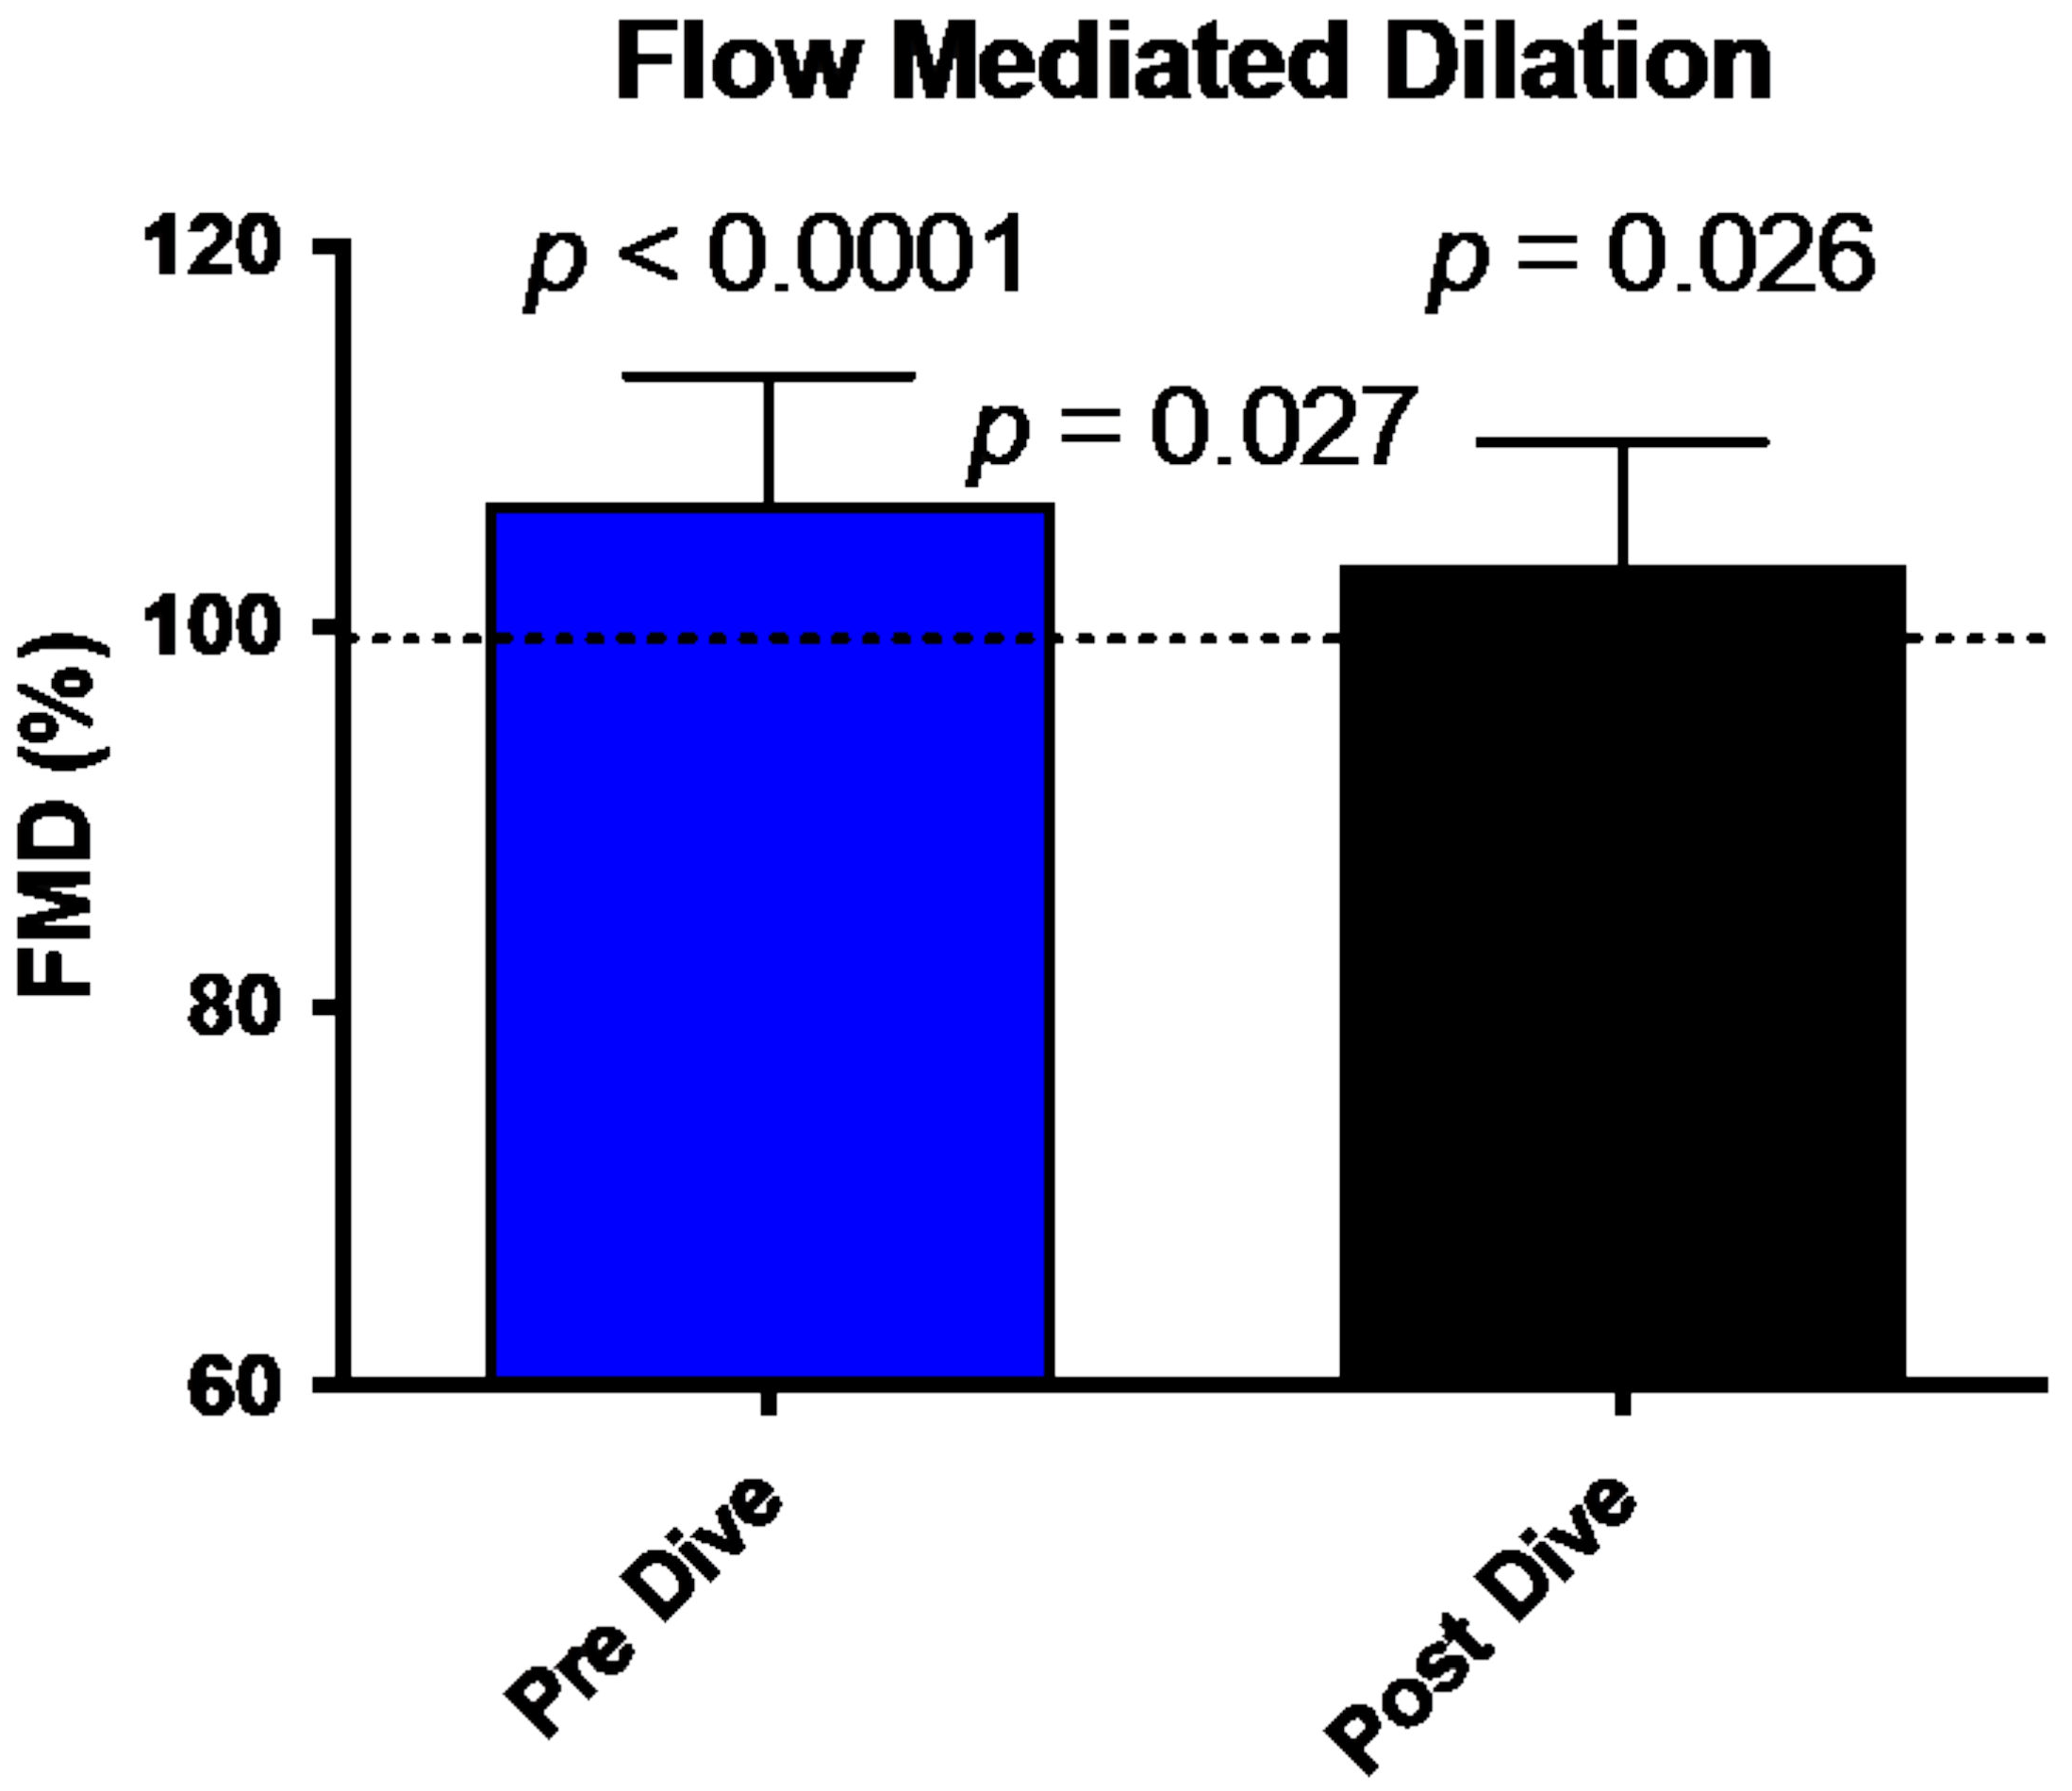

2.2. Data Acquisition

5.2. Flow-Mediated Dilation (FMD) and Vascular Gas Emboli

- Lambrechts, K.; Pontier, J.-M.; Balestra, C.; Mazur, A.; Wang, Q.; Buzzacott, P.; Theron, M.; Mansourati, J.; Guerrero, F. Effect of a single, open-sea, air scuba dive on human micro- and macrovascular function. Eur. J. Appl. Physiol. 2013, 113, 2637–2645. [Google Scholar] [CrossRef]

- Lambrechts, K.; Balestra, C.; Theron, M.; Henckes, A.; Galinat, H.; Mignant, F.; Belhomme, M.; Pontier, J.-M.; Guerrero, F. Venous gas emboli are involved in post-dive macro, but not microvascular dysfunction. Eur. J. Appl. Physiol. 2017, 117, 335–344. [Google Scholar] [CrossRef]

- Obad, A.; Valic, Z.; Palada, I.; Brubakk, A.O.; Modun, D.; Dujić, Z. Antioxidant pretreatment and reduced arterial endothelial dysfunction after diving. Aviat. Space Environ. Med. 2007, 78, 1114–1120. [Google Scholar] [CrossRef]

- Brubakk, A.O.; Duplancic, D.; Valic, Z.; Palada, I.; Obad, A.; Bakovic, D.; Wisløff, U.; Dujic, Z. A single air dive reduces arterial endothelial function in man. J. Physiol. 2005, 566, 901–906. [Google Scholar] [CrossRef] [Green Version]